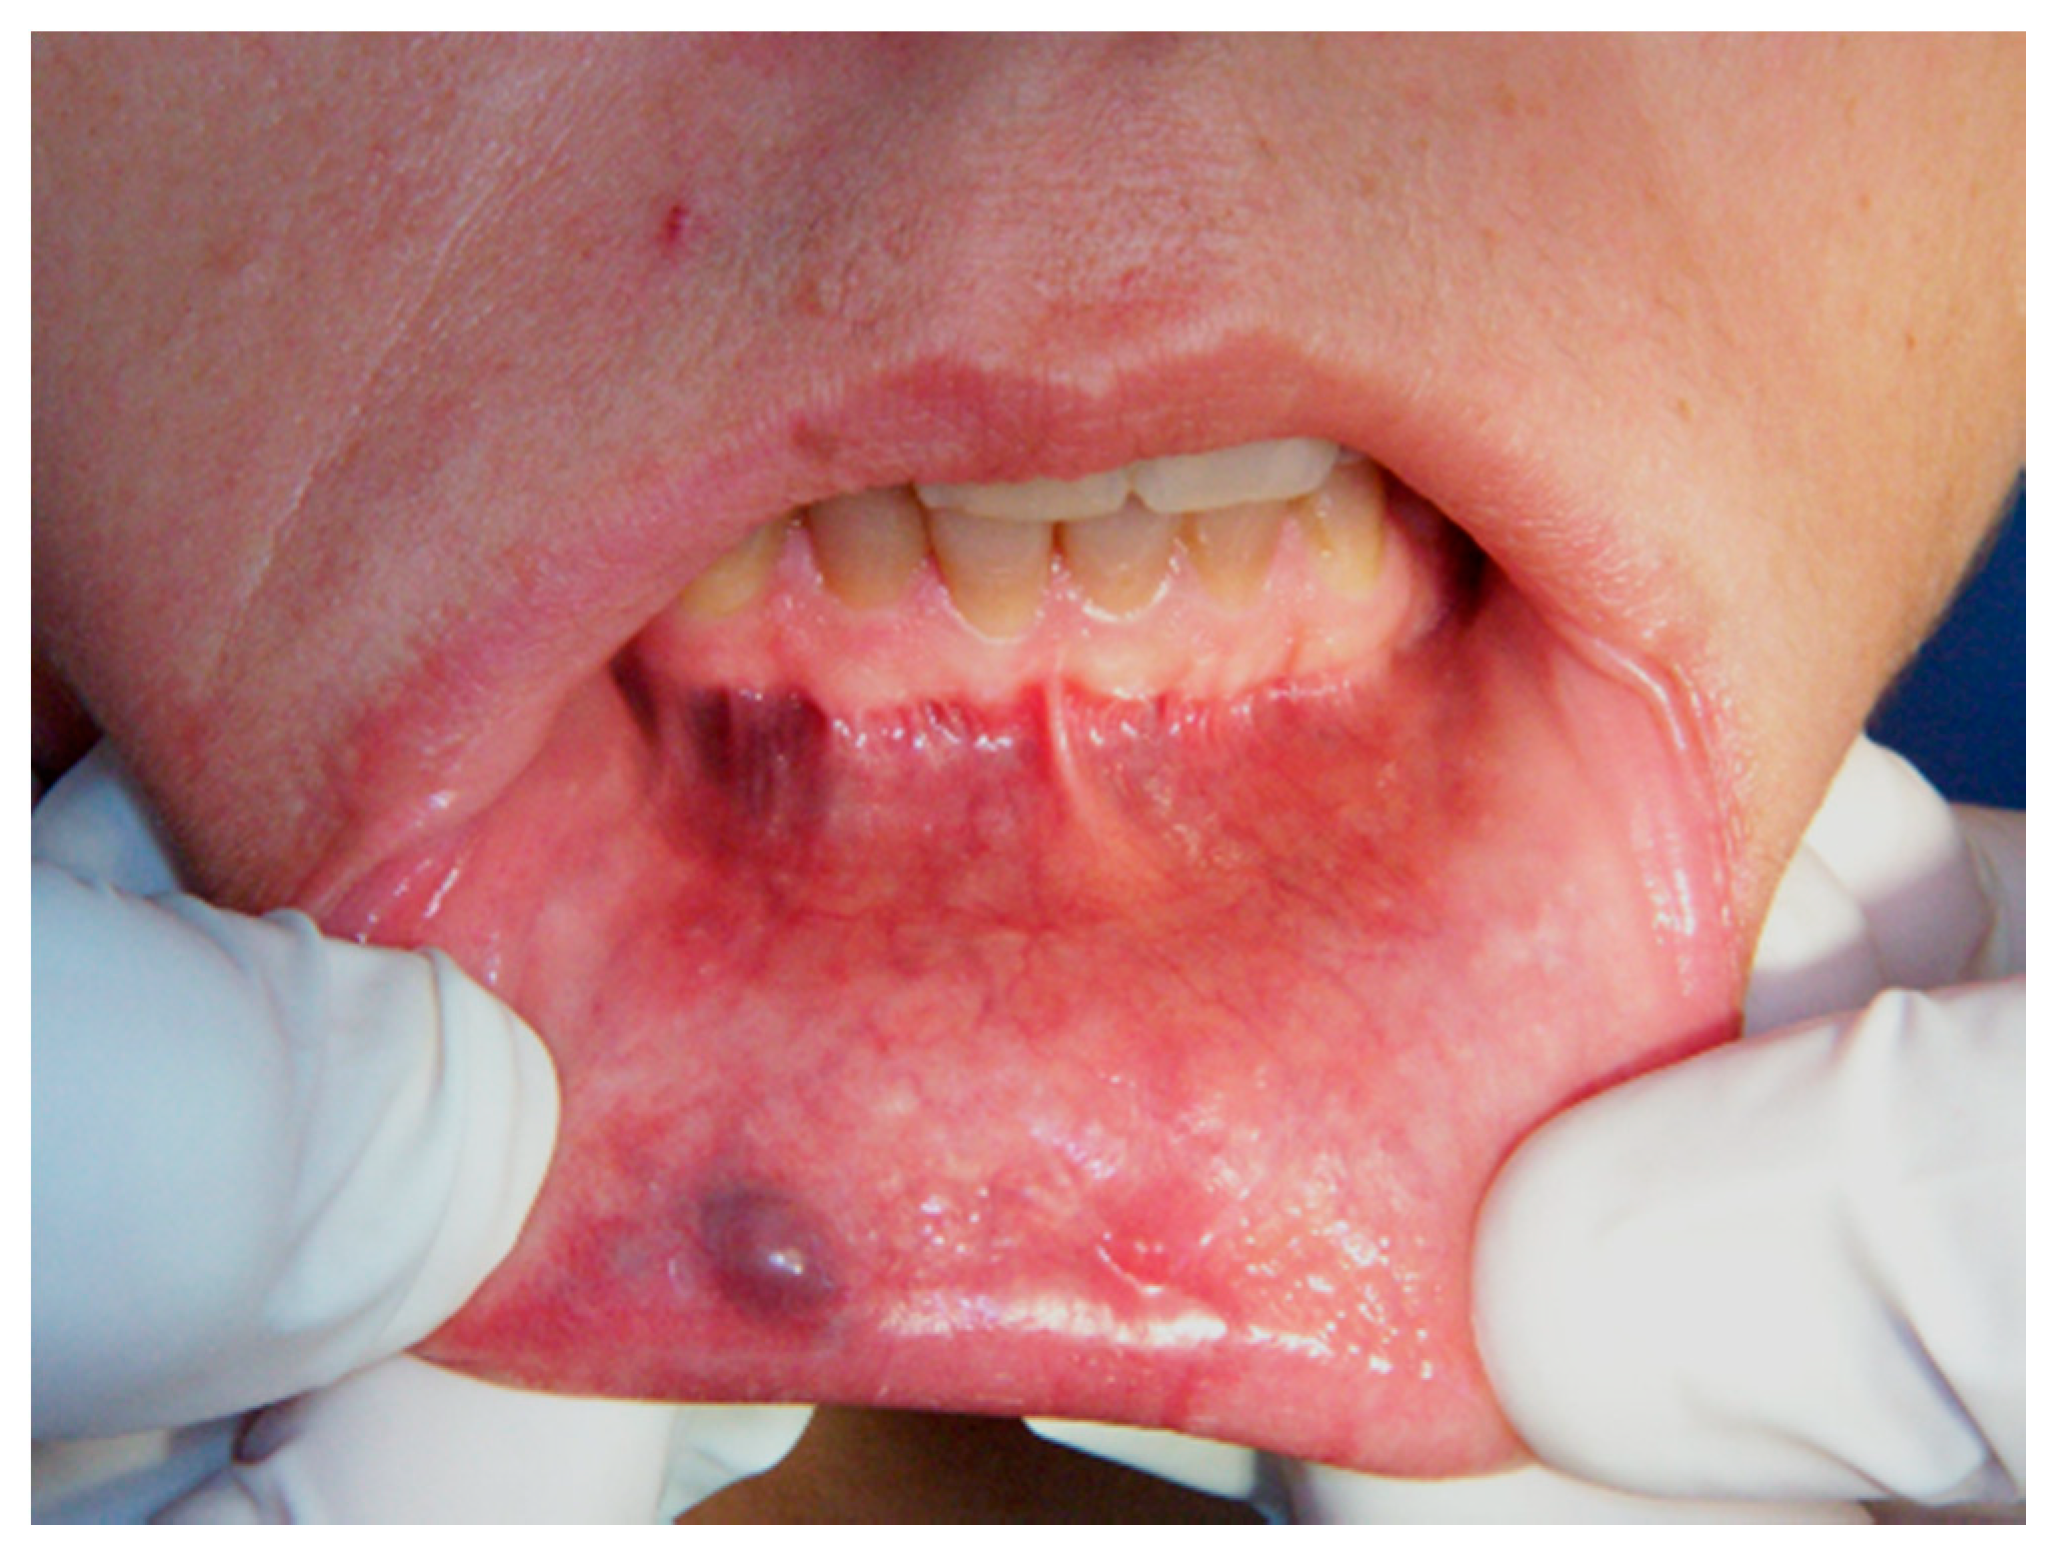

Aesthetic Treatment Outcomes of Capillary Hemangioma, Venous Lake, and Venous Malformation of the Lip Using Different Surgical Procedures and Laser Wavelengths (Nd:YAG, Er,Cr:YSGG, CO2, and Diode 980 nm)

1. Introduction